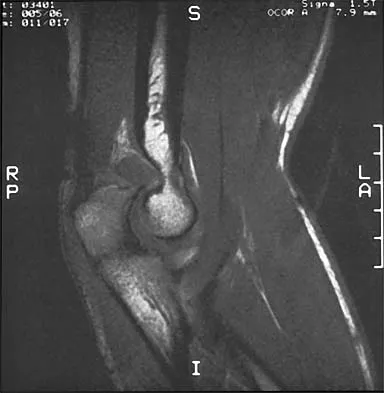

Figures 8a through 8c show the lateral radiograph and T1- and T2-weighted MRI scans of a 14-year-old soccer player who reports aching thigh pain. The next most appropriate step in management should consist of

Although the MRI findings could be misinterpreted as an aggressive soft-tissue process, the periosteal-based ossification on the radiograph in an athlete most likely suggests myositis ossificans. The radiograph should be repeated to see further maturation of the ossification with a typical "zoning" pattern. The zoning pattern is one of peripheral ossification. This is often best seen on a CT scan. King JB: Post-traumatic ectopic calcification in the muscles of athletes: A review. Br J Sports Med 1998;32:287-290.